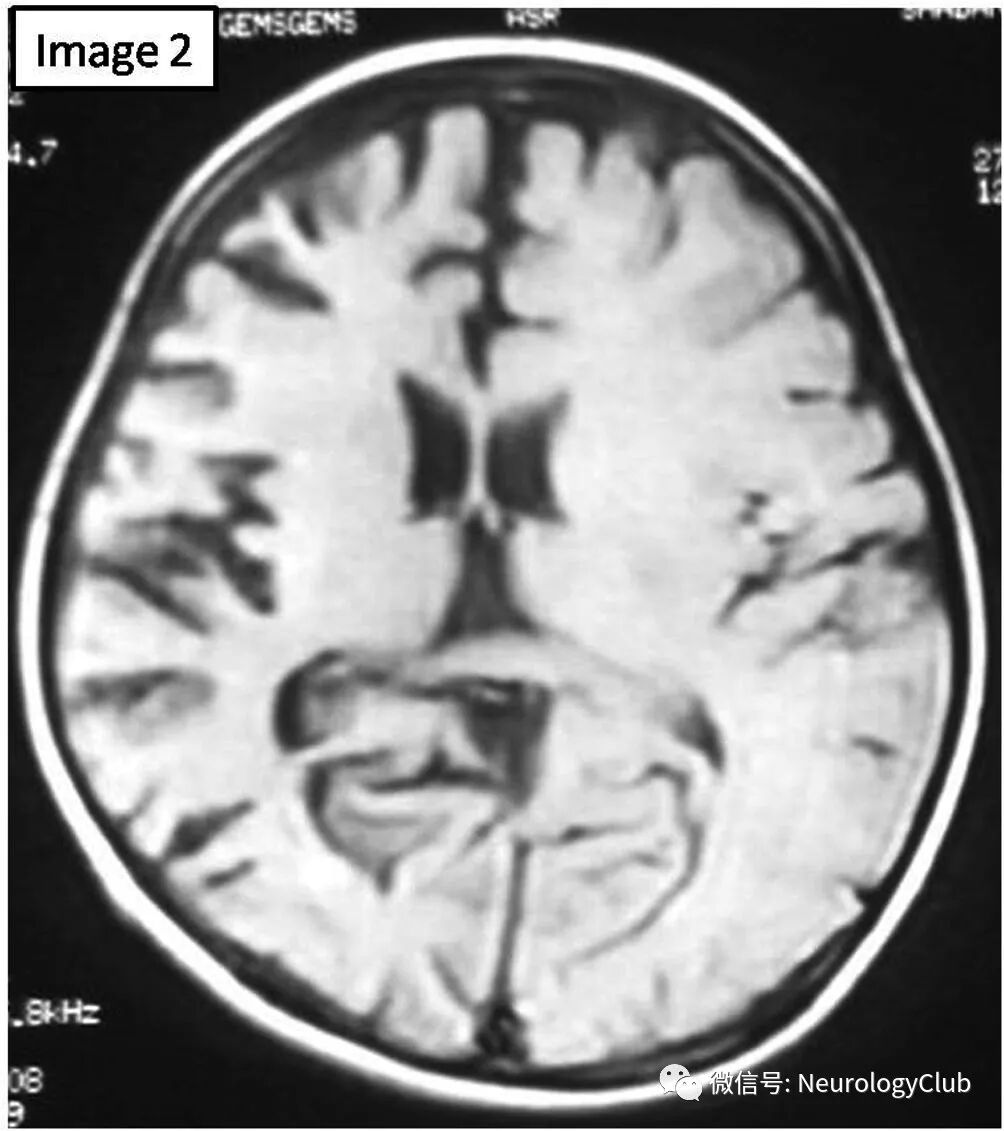

查体未见颜面部畸形或皮肤异常,高级认知功能缺损(记忆力,判断力,抽象思维和计算力),累及左侧面部和上下肢的部分性癫痫持续状态,左侧肢体无力,远端明显。未见其他不自主运动。视野检测提示同向偏盲。脑电图提示右侧半球为主的背景明显慢化。行头颅MRI检查,T2WI可见右侧脑沟增宽,右侧侧脑室扩大,右侧尾状核头萎缩(图1);T1WI可见类似表现符合右侧大脑半球萎缩(图2)。

(图2:T1WI可见右侧大脑半球脑沟增宽,右侧三脑室扩大,提示右侧大脑半球萎缩)